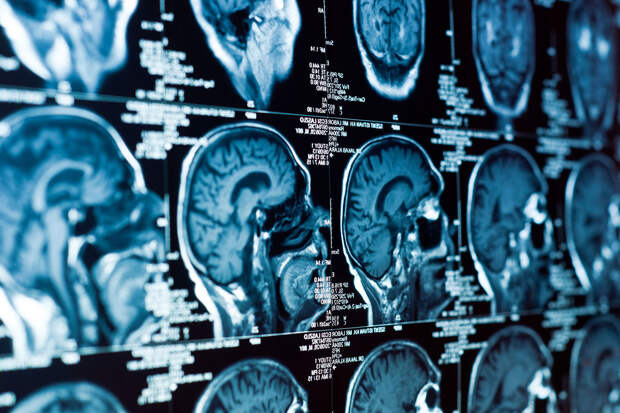

Ученые США предложили новый способ доставки противоопухолевых лекарств против глиобластомы — одного из самых агрессивных видов рака мозга. Метод основан на назальном введении специальных наноструктур, способных активировать иммунный ответ в опухоли. Работа опубликована в PNAS (Proceedings of the National Academy of Sciences).

Глиобластома зачастую плохо реагирует на терапию, в том числе из-за так называемой "холодной" иммунной среды: присутствие опухоли практически не активизирует естественную защиту организма. Усилить иммунитет может активация особого внутриклеточного пути STING. Однако препараты, воздействующие на него, быстро разрушаются и требуют прямого введения в опухоль, что делает лечение крайне сложным и инвазивным.